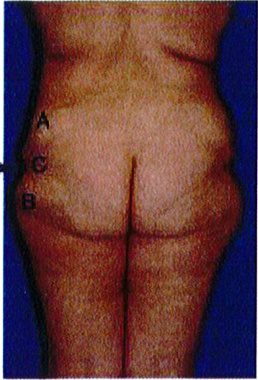

Square shape

Hình. 26. (A) Đánh giá độ chùng của da mông ở các vị trí với các hình dạng khác nhau. Bệnh nhân bên trái bị lõm nghiêm trọng ở điểm C và vùng ngoài da tương đối sần sùi. Cô ấy nên được điều trị bằng các pp nâng mông. 3 bệnh nhân còn lại xuất hiện vùng da thừa và nếp nhăn ở điểm B và C. (B) Bệnh nhân ở ảnh ngoài cùng bên phải của hình 26A sau khi trải qua phẫu thuật nâng mông trên bằng vạt da. Ở thì hai của cuộc phẫu thuật, cô ấy đã được nâng nếp lằn mông và làm đầy bằng implant.